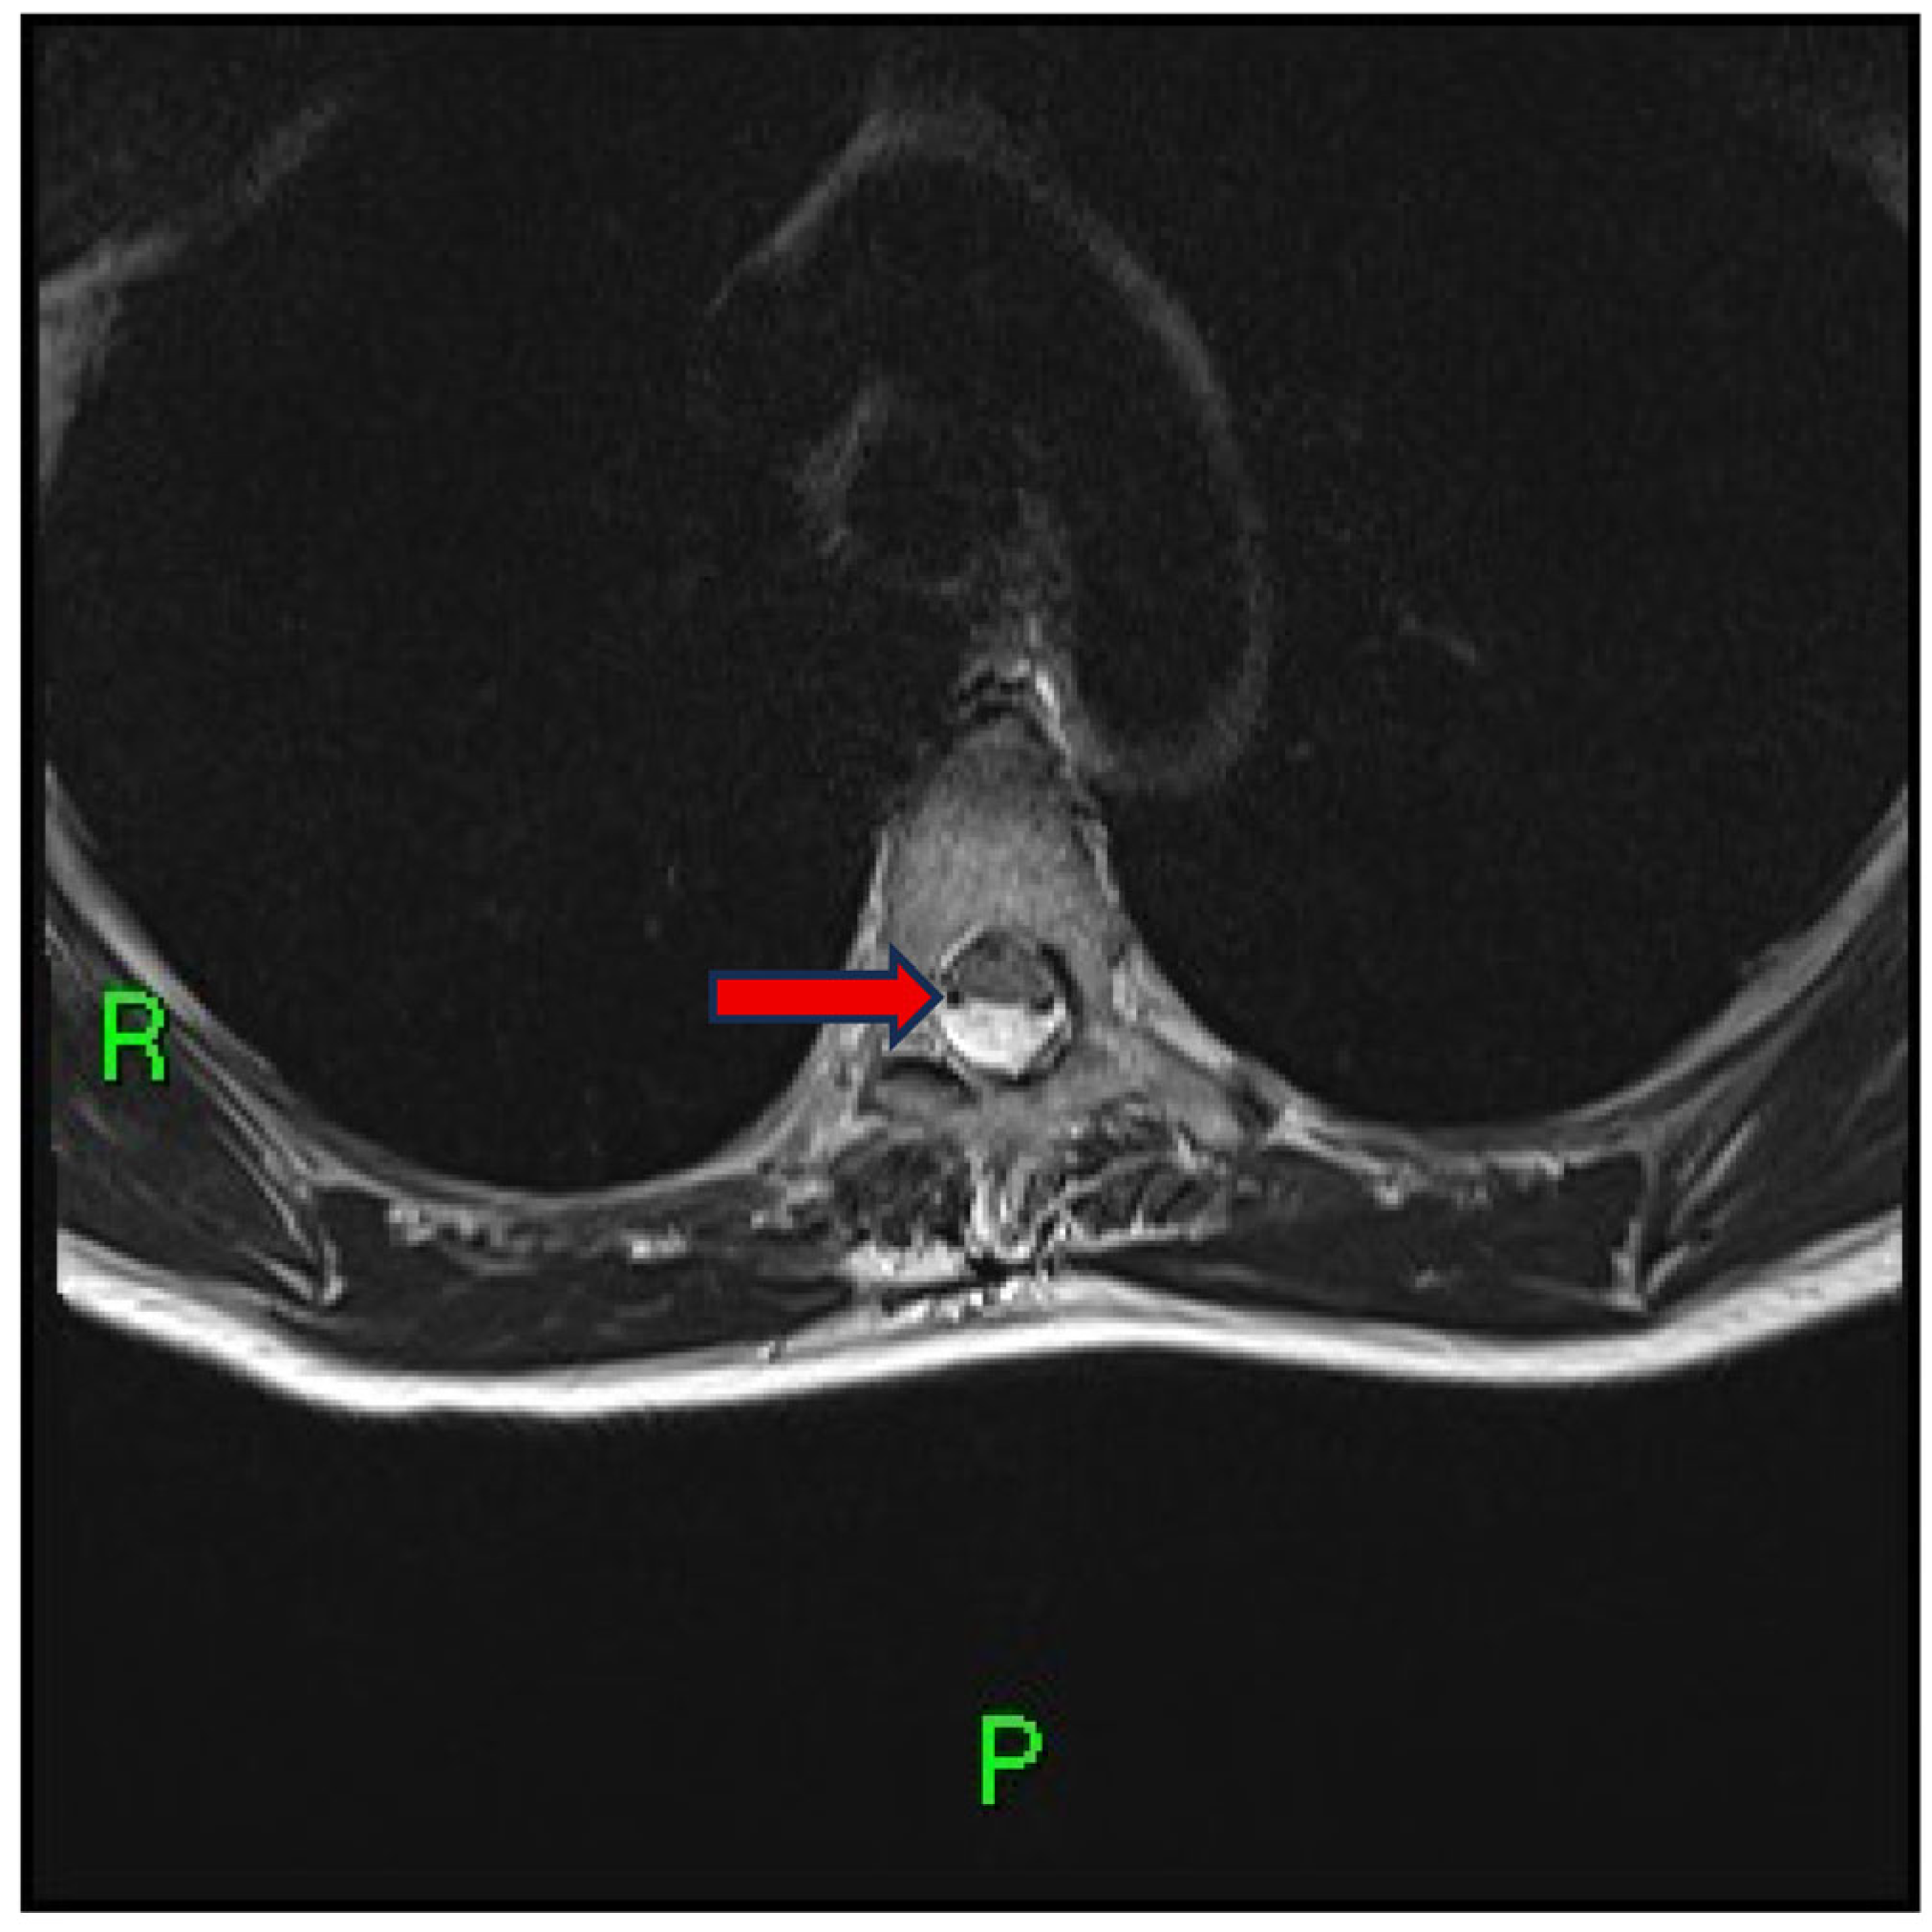

- Reardon, M.A.; Raghavan, P.; Carpenter-Bailey, K.; Mukherjee, S.; Smith, J.S.; Matsumoto, J.A.; Yen, C.P.; Shaffrey, M.E.; Lee, R.R.; Shaffrey, C.I.; et al. Dorsal thoracic arachnoid web and the “scalpel sign”: A distinct clinical-radiologic entity. AJNR Am. J. Neuroradiol. 2013, 34, 1104–1110. [Google Scholar] [CrossRef] [PubMed]

- Arora, V.; Verma, H.; Kamal, R.; Lone, N.A. Dorsal arachnoid web: The ‘scalpel’ sign—A case report and differential diagnosis. Egypt. J. Radiol. Nucl. Med. 2022, 53, 163. [Google Scholar] [CrossRef]

- Brasil, P.; Pereira, L.; Távora, D.; Camara, A.; Filho, C.M.; Coimbra, P. Imaging findings in dorsal thoracic arachnoid web and the differential diagnosis of “Scalpel Sign”. Neurographics 2020, 10, 96–102. [Google Scholar] [CrossRef]

- Mukherjee, S.; Reardon, M.A.; Raghavan, P. Dorsal thoracic arachnoid web: Another intradural entity with ventral cord displacement. RadioGraphics 2015, 35, 297–298. [Google Scholar] [CrossRef] [PubMed]